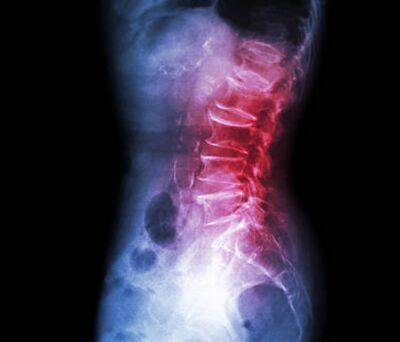

- Low back: lumbar stenosis, lumbar disc herniation, sciatica (lumbar radiculopathy), foraminal narrowing.

Lumbar

Stenosis

Low back · Leg pain

Lumbar Disc

Herniation

Slipped disc · Sciatica

Lumbar

Radiculopathy (Sciatica)

Leg pain · Numbness